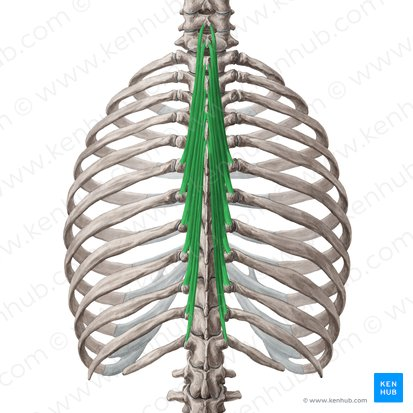

m semispinalis (thoracis)

mm multifidi

mm rotatores